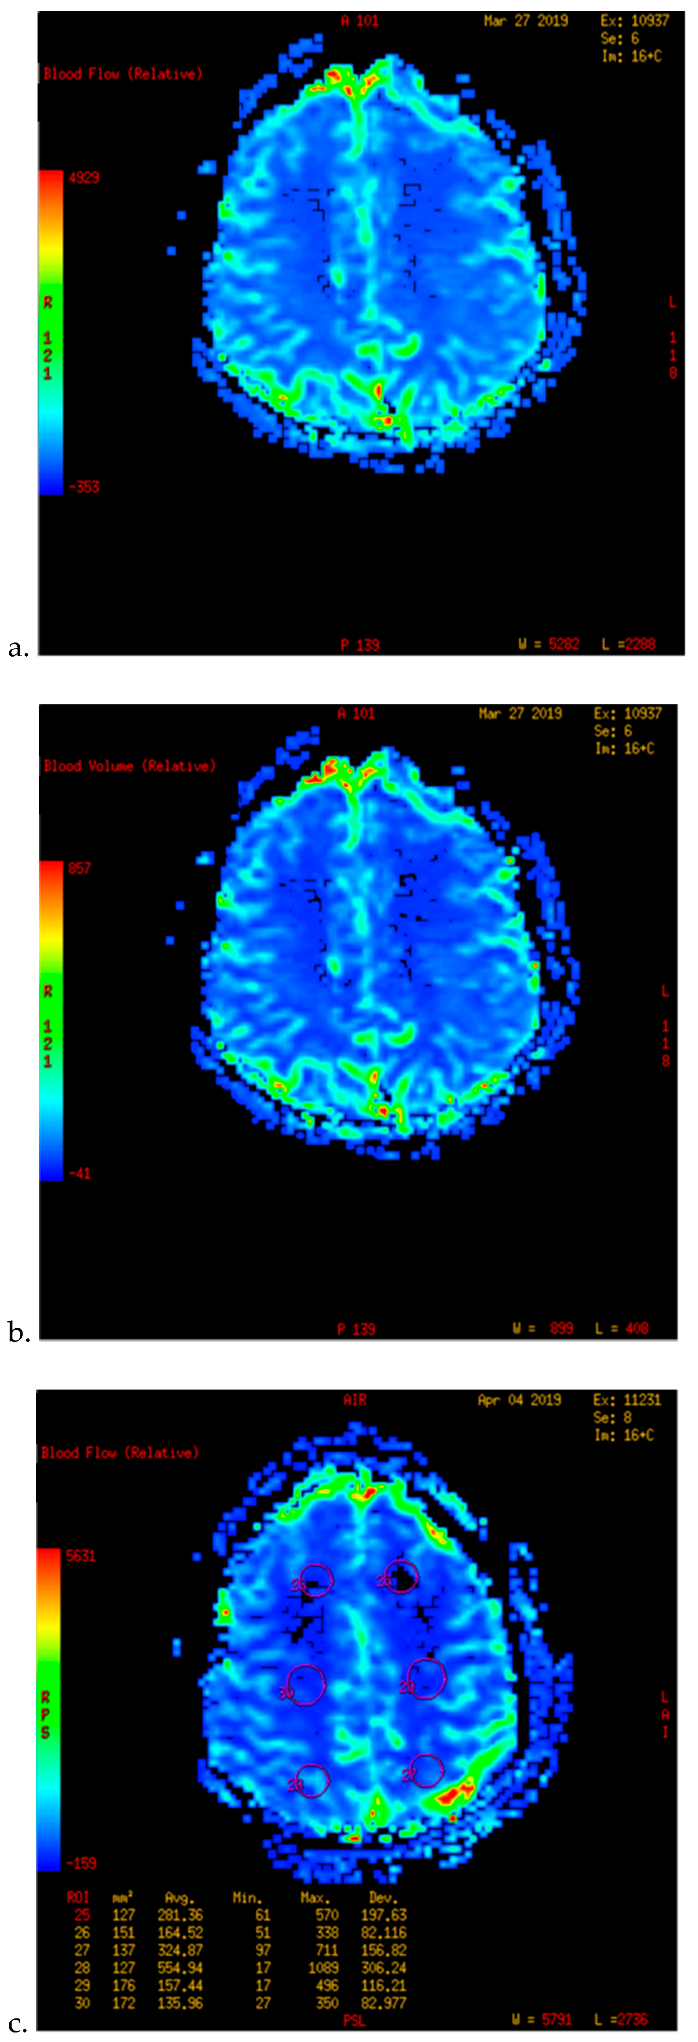

- Kameyama, M.; Fujimura, M.; Tashiro, R.; Sato, K.; Endo, H.; Niizuma, K.; Mugikura, S.; Tominaga, T. Significance of Quantitative Cerebral Blood Flow Measurement in the Acute Stage after Revascularization Surgery for Adult Moyamoya Disease: Implication for the Pathological Threshold of Local Cerebral Hyperperfusion. Cerebrovasc. Dis. 2019, 48, 217–225. [Google Scholar] [CrossRef]

- Tu, X.K.; Fujimura, M.; Rashad, S.; Mugikura, S.; Sakata, H.; Niizuma, K.; Tominaga, T. Uneven cerebral hemodynamic change as a cause of neurological deterioration in the acute stage after direct revascularization for moyamoya disease: Cerebral hyperperfusion and remote ischemia caused by the ‘watershed shift’. Neurosurg. Rev. 2017, 40, 507–512. [Google Scholar] [CrossRef]